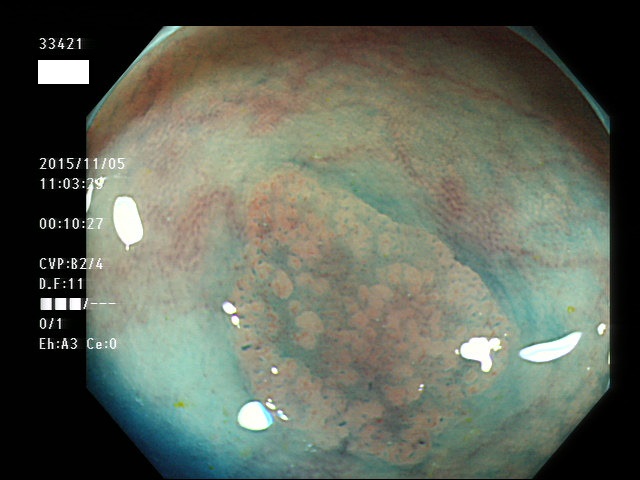

上記100名より抽出した平坦・陥凹型腺腫(=癌化の危険が高いが見落としやすい病変)の内視鏡写真